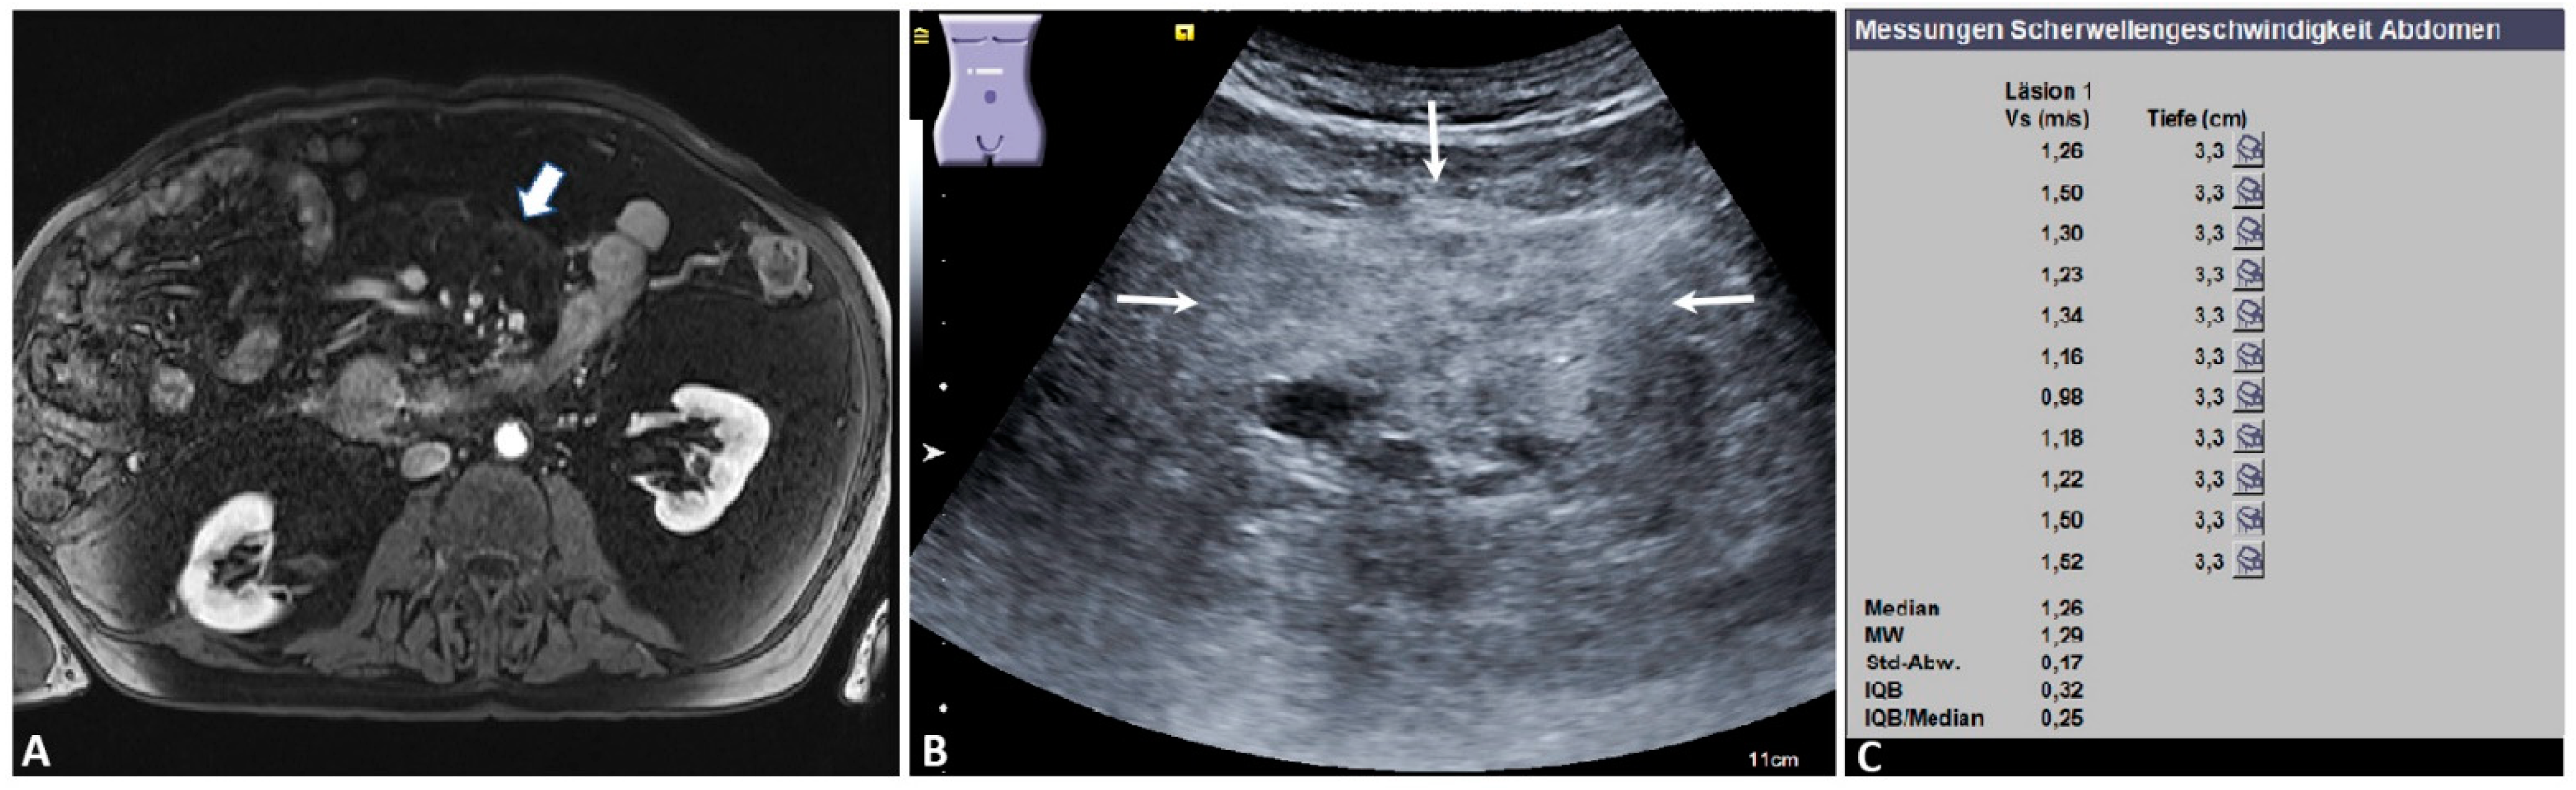

Figure 1.

Benign mesenteric mass. An 80-year-old male patient with a known history of type 1 autoimmune pancreatitis under immunosuppressive treatment. (A) Magnetic resonance imaging appearance of a mass-like “misty mesentery” in the right upper portion of the umbilical region (arrow) (courtesy of Prof. Dr. Mahnken, Department of Radiology, University Hospital Marburg); (B) the ultrasound appearance of an ill-defined, slightly inhomogeneous, echogenic mesenteric mass (arrows); (C) the final acoustic radiation force impulse (ARFI) report of the same mass, showing a mean ARFI velocity (MW) of 1.29 m/s. The mesenteric histology showed an IgG−4-positive sclerosing mesenteritis. Läsion 1: lesion 1; Vs (m/s): velocity in meter per second; Tiefe (cm): depth in centimeter; MW = mean value (Mittelwert); Std-Abw.: standard deviation (Standard Abweichung); IQB: interquartile range (Interquartilbereich).